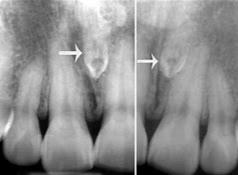

这种情况大多是因为多生牙,比较常见的是长在门牙之间的牙。这种多余的牙形状就比较随便了,比如锥形的、柱形、没长出来的。

也不全是我们能看到的,有埋伏于颌骨里的,还有少数会长在鼻腔、上颌窦内。

因为开始也没啥症状,有时家长会误以为这只是孩子门牙牙缝大而已。那多长的要不要拔呢?这个需要让专业医生拍片确认是多生牙后,如果评估后是影响牙齿排列和颌骨发育的“多生牙”,是建议尽早拔除的。